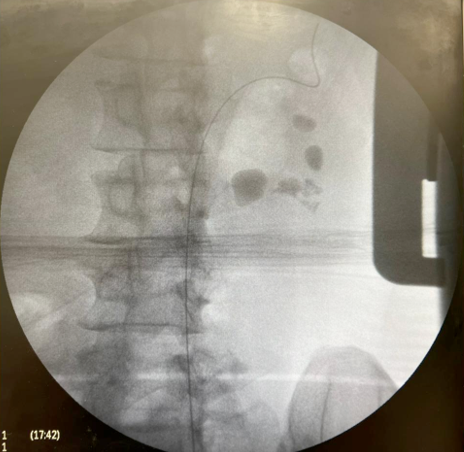

Sequência do tratamento:

Imagem Inicial e final:

-Tempo cirúrgico – 94 minutos

-Alta no 1oPO

-Retirada do Duplo J no 7o PO

-Eliminou vários pequenos fragmentos

-TC com 30 dias – livre de cálculo